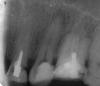

shishok Опубликовано 19 августа, 2009 Поделиться Опубликовано 19 августа, 2009 А не жалко портить под коронку хороший зуб(27)? Кстати,доктора,а на корне 25 не перелом ли ? Ссылка на комментарий

Serg1977 Опубликовано 19 августа, 2009 Автор Поделиться Опубликовано 19 августа, 2009 (изменено) А не жалко портить под коронку хороший зуб(27)? Кстати,доктора,а на корне 25 не перелом ли ? а он у меня все равно в воздухе висит ибо 37 удален. про перелом вы меня напугали, вот снимок в бОльшем качестве, при постукивании по зубам болел именно 26 и кусать больно было именно на него. никаких травм не было. http://pic.ipicture.ru/uploads/090819/12837/thumbs/kM8qIRKfTs.jpg PS а что скажете про возможность резекции и ратроградного пломбирования каналов? или верхняя челюсть и расположение зуба делает доступ к верхушкам корней практически невозможным? PPS а удалять я еще и опасаюсь - когда удаляли 37 анастезия подействовала только на верхний язычок и щеку, слез из глаз в результате натекло больше чем крови. все остальные операции во рту сейчас делаю без нее, ибо стараюсь не запускать, хожу два раза в год на осмотр и т.п. Изменено 19 августа, 2009 пользователем Serg1977 Ссылка на комментарий

Zlata-doctor Опубликовано 20 августа, 2009 Поделиться Опубликовано 20 августа, 2009 26-удалять, значительный воспалительный процесс, очаг хронической инфекции ( а значит инфекция будет гулять по всему организму и неизвестно, где остановиться). Будете играться с ним, перелечивать, притушивать это воспаление, вкладывать деньги и надеяться, что все восстановиться-только потеряете время. Для резекции тоже нет показаний, обширная деструкция, все вмешательства только отсрочат ненадолго удаление. Ссылка на комментарий

Doktor Max Опубликовано 20 августа, 2009 Поделиться Опубликовано 20 августа, 2009 желаете себе проблем - оставляйте зуб.гарантий,что каналы такого зуба перелечат,нет никаких.Проблемы на этой 6ке были и 4 года назад- воспаление на дистальном корне на сегодняшний день увеличилось до размеров как минимум кистогранулемы. при таком раскладе и до гайморита недалеко.А это уже гораздо серьезнее.так что удалите и живите спокойно. А хороший имплантант лучше плохого зуба. Ссылка на комментарий